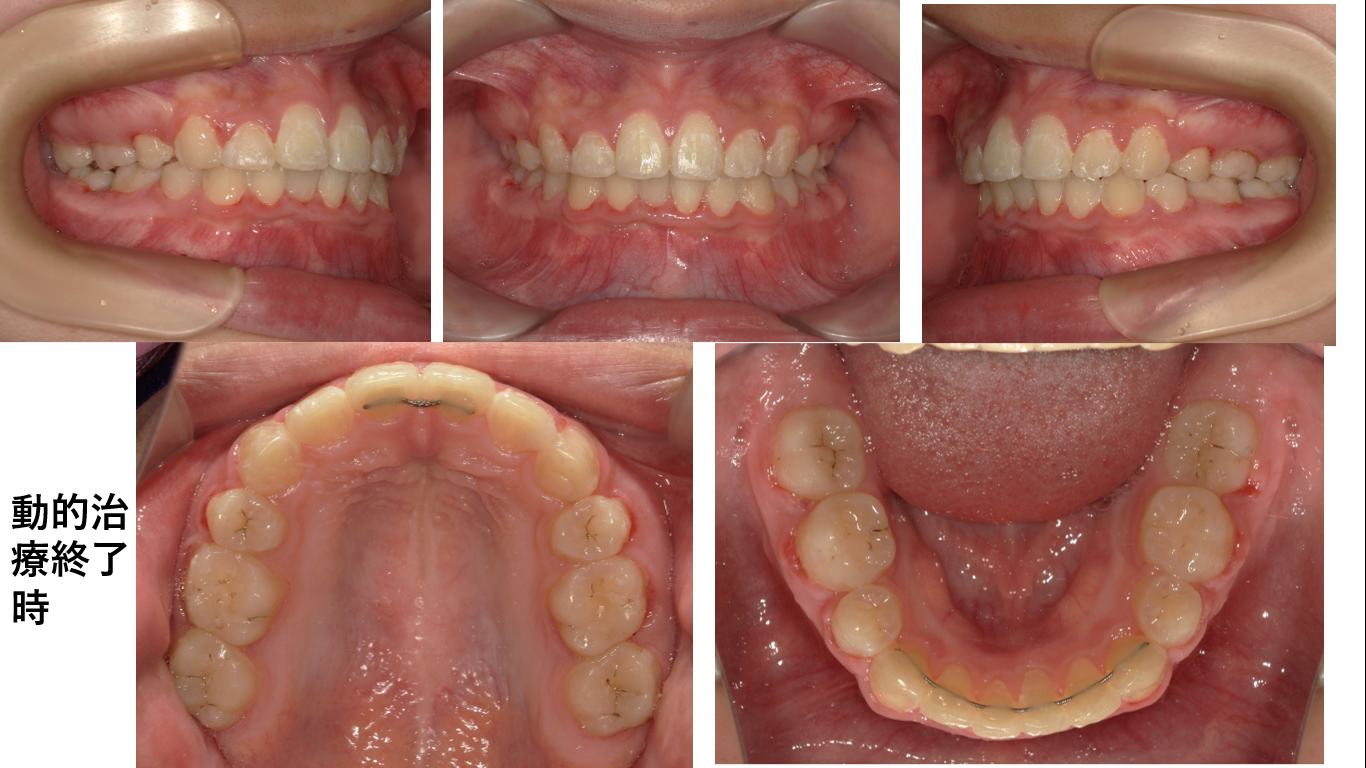

矯正症例149 AngleⅠ級上顎前突

初診時12歳 治療期間2年6か月、抜歯部位:上下顎左右4番、治療費総額112万円(税込み)